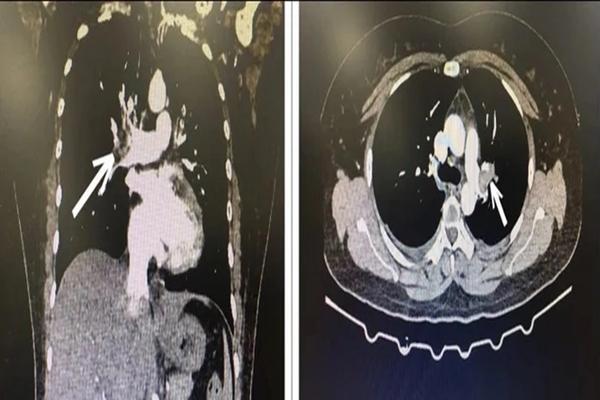

Hình ảnh chụp CT lồng ngực bệnh nhân

Do đó, các bác sĩ quyết định cho bệnh nhân chụp CT ngực có tiêm thuốc cản quang, kết quả là hình ảnh huyết khối động mạch phổi 2 bên.